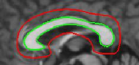

Figure 12: Segmentation of corpus callosum images in sagittal plane T1-weighted brain magnetic resonance images taken from [37]. For all images, the same template was used and initialized in a manner similar to the way shown in the top left corner image. The converged results using the proposed shape template approach and the result obtained on subsequent refinement using snake energies[22] are displayed alongside.

In Figure 12, we show the results obtained for segmentation of corpus callosum in T1-weighted MR images. Many techniques on segmentation of corpus callosum are affected by the adjoining fornix structure due to the similarity in intensities. However, it can be observed from the results that the proposed snake is less affected by the fornix. We further refine results obtained using the proposed technique with gradient energies[22]. We display the results obtained on refinement alongside the output from the proposed shape-based approach.